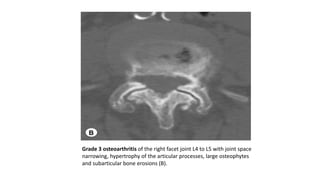

Grading Facet Joint Osteoarthritis. CT at L3 to L4 (A) and L4 to L5 (B). Grade 1 osteoarthritis of the right facet

joint L3 to L4 (mild hypertrophy) and grade 2 osteoarthritis of the left facet joint (narrowing of the joint space,

moderate hypertrophy and osteophytes, subarticular erosion) (A).

Grade 3 osteoarthritis of the right facet joint L4 to L5 with joint space

narrowing, hypertrophy of the articular processes, large osteophytes

and subarticular bone erosions (B).